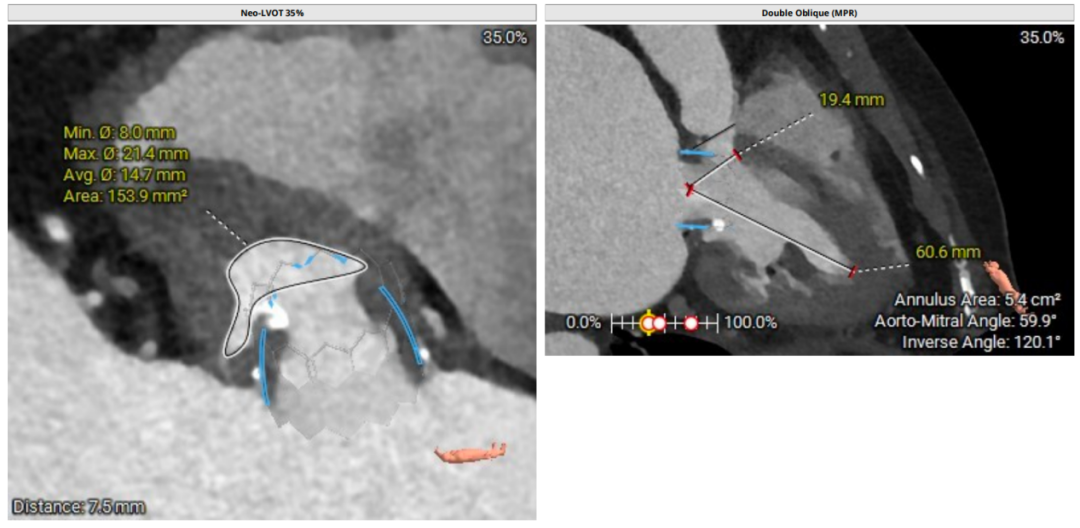

术前CT评估

二尖瓣生物瓣支架内径 26.5mm,结合瓣架形态、瓣架高度及手术记录,符合EPIC 27#。瓣中瓣治疗考虑选择25# 介入瓣膜。模拟25# 瓣膜植入,测得NEO-LVOT 面积155.8mm²,术后存在新流出道梗阻风险。左心耳尖端未见血栓。左心房增大73.4*118.7mm,房间隔未见增厚,未见明显钙化,靠后靠下房间隔穿刺点距二尖瓣水平高度27.7mm,房间隔穿刺点高度可。